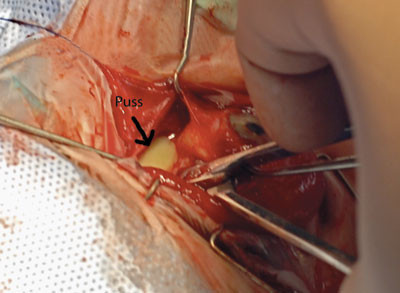

Pasienten ble operert samme kveld. Den periorbitale abscessen ble tømt, og det ble sydd fast et bølgedren. Det ble deretter gjort bilateral åpning av fremre etmoidalsinus og antrostomi til maxillarsinus. Vi fant store mengder puss i alle sinuser. Dyrkning av bakterieundersøkelse fra lokalsykehus viste oppvekst av anaerobe staver.

Ny operasjon ble gjennomført, nå sammen med øyelege (fig 4). Conjunctiva ble løsnet medialt mot bulbus og man gikk stumpt bakover til man traff på abscessen mellom mediale rectusmuskulatur og nervus opticus (fig 5). Vi gikk deretter inn i de to foregående abscesshulene, skylte godt og la inn to nye bølgedren. Denne gang normaliserte infeksjonsprøvene seg umiddelbart, og kliniske symptomer gikk raskt i regress. Kontroll-CT med kontrast to dager postoperativt viste nå ingen tegn til abscess. Bakterieundersøkelse med resistensbestemmelse av den første abscessen viste oppvekst av Streptococcus anginosus (Milleri), en abscessogen mikrobesom var sensitiv for penicillin G, og vekst av Fusobacterium necroforum (anaerob),som var sensitiv for metronidazol. Ciprofloksacin ble seponert. Alle dren ble fjernet to dager etter siste operasjon. Synet normaliserte seg, proptosen gikk tilbake og konjunktival blandingsinjeksjon ble behandlet med kloramfenikol salve i en uke. Han ble utskrevet, og videre kontroller skjedde på pasientens lokalsykehus. Ved telefonisk kontakt med pasienten ett år senere hadde han ingen sekveler etter sykdomsforløpet.